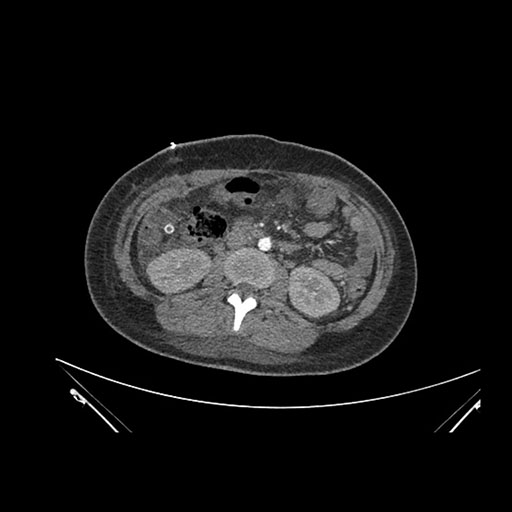

Axial Arterial

Imaging analysis

Based on initial findings, which issue(s) would you be most concerned about?